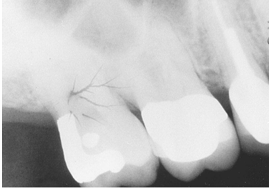

What is the problem with this STATIC ELECTRICITY X-ray?

Appears with thin, black, branching lines, Occurs when a film packet is opened quickly, Occurs when a film pack is opened before radiographer touches a conductive object

How would you resolve this STATIC ELECTRICITY X-ray?

Open film packets slowly, Touch a conductive object before unwrapping films when in a carpeted office